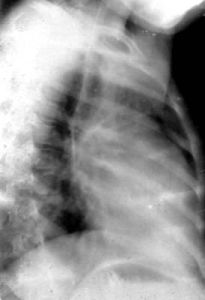

右心室增大即後前位,可見心腰平直或隆起,肺動脈段延長,因而相反搏動點下移。心橫徑增大,主要向左擴展。左心室受壓推移,心尖可由右心室構成,呈鈍圓形,嚴重時可向上翹。右心室向右擴展,可將右心房推向右上方。增大顯著時,心向左鏇轉,這下前方胸骨阻力、左心相對游離和右心較為固定等因素有關。鏇轉後,心腰更加突出,心室段可完全由右心室前壁組成,主動脈球則不明顯。